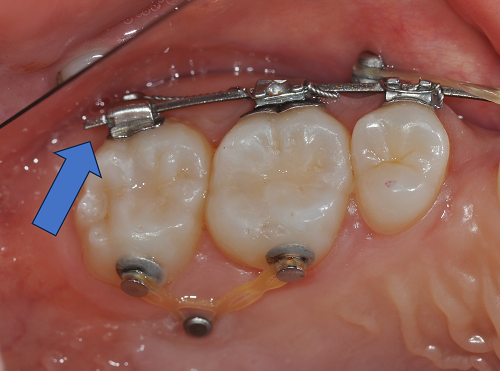

와이어 끝이 찔릴 때 생기는 불편감

교정 중 많이 호소하시는 또 다른 불편감이 바로 와이어 찔림입니다.

다행히 월진료를 규칙적으로 받으시면, 내원 시마다

튀어나온 와이어를 잘라내거나

끝을 둥글게 다듬어 드리기 때문에

대부분 심한 불편감 없이 지내실 수 있습니다.

와이어 찔릴 때 대처 방법

병원 내원 후 와이어 정리

교정용 왁스 사용 (응급·자가 대처)

내원 전 임시 처치로,

와이어가 튀어나온 부위

잘 붙이는 팁:

왁스를 붙일 부위를 면봉/티슈 등으로 먼저 “마른 상태”로 만들어 준 뒤 왁스를 부착하면 훨씬 오래 버텨줍니다.